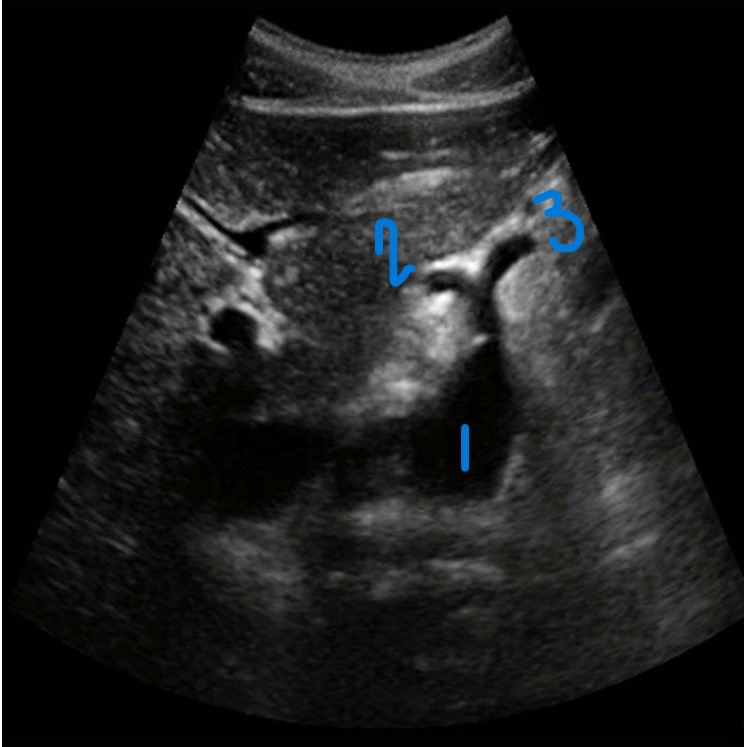

<p>In this Sagittal-Coronal plane, what is #1?</p>

In this Sagittal-Coronal plane, what is #1?

<p>In this Sagittal-Coronal plane, what is #2?</p>

In this Sagittal-Coronal plane, what is #2?

<p>In this Sagittal-Coronal plane, what is #3?</p>

In this Sagittal-Coronal plane, what is #3?

<p>What number is known as the RRA</p>

What number is known as the RRA

<p>What is this structure?</p>

What is this structure?

The right and left renal arteries